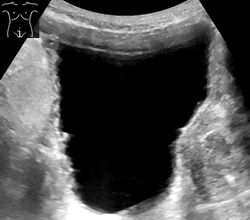

Ultrasonography showing a trabeculated wall, seen as small irregularities mainly at left (superior part). This is strongly associated with urinary retention.[7]

Analysis of urine flow may aid in establishing the type of micturition (urination) abnormality. Common findings, determined by ultrasound of the bladder, include a slow rate of flow, intermittent flow, and a large amount of urine retained in the bladder after urination. A normal test result should be 20-25 mL/s peak flow rate. A post-void residual urine greater than 50 ml is a significant amount of urine and increases the potential for recurring urinary tract infections.[citation needed] In adults older than 60 years, 50-100 ml of residual urine may remain after each voiding because of the decreased contractility of the detrusor muscle.[6] In chronic retention, ultrasound of the bladder may show massive increase in bladder capacity (normal capacity is 400-600 ml).[citation needed]